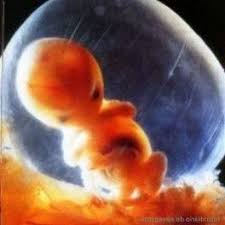

Semana 8 de embarazo. Uno de los hechos más importantes es que se empiezan a visualizar los rasgos faciales del embrión tales como la forma de la nariz el labio superior las orejas y los párpados. El bebé de 8 semanas de embarazo tiene el tamaño de una frambuesa es decir imagínate es tan diminuto que su tamaño es como la de una bola de goma de mascar. Ya deberías haber contactado con tu obstetra.

Además pesa cerca de 025 g y mide aproximadamente entre 7 y 17 mm más o menos media pulgada. En la semana 8 se empieza a formar la piel del embrión que es translúcida y. Riesgo de aborto en la semana 8 de embarazo.

Al final de esta octava semana de embarazo todos los sistemas y órganos importantes estarán formados aunque algunos estén en fases iniciales de desarrollo. El embrión crece a un ritmo trepidante.